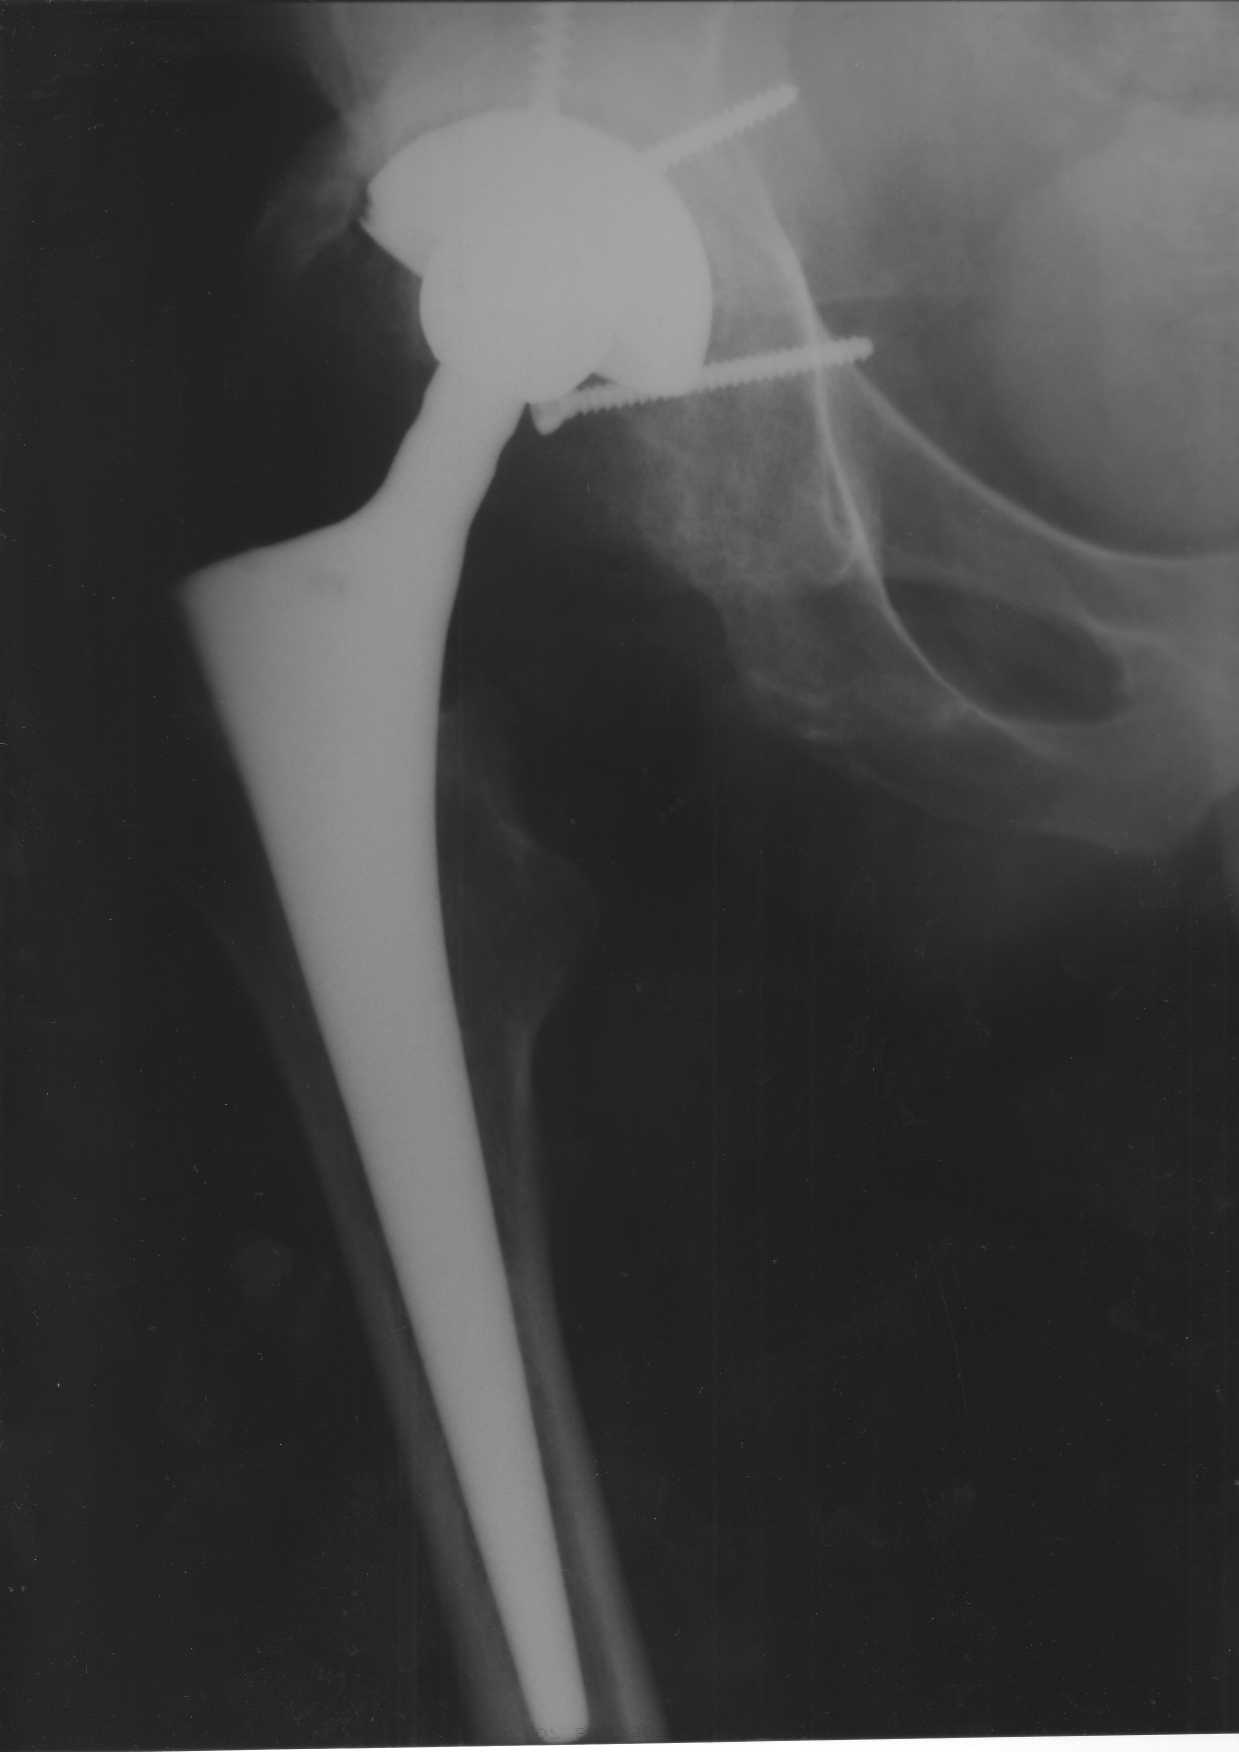

Уважаемые коллеги.В 3 Центральный Военный Клинический Госпиталь имени А. А. Вишневского, что в Красногорске, Московской области, в отделение эндопротезирования крупных суставов поступил пациент 1960 года рождения Жалобы при поступлении: на боли в области левого тазобедренного сустава (больной указывает на точку расположенная в середине условной линии между седалищным бугром и большим вертелом), усиливающиеся в начале ходьбы, при опоре на левую ногу с иррадиацией болей по наружной и наружно-задней поверхности левого бедра, левый коленный сустав; снижение объема движения в левом тазобедренном суставе, снижение опорной способности левой нижней конечности, хромоту на левую ногу, необходимость использования дополнительной опоры (костыли) при ходьбе, снижение объема двигательной активности из за болей в суставе.В анамнезе: Со слов больного, согласно медицинских документов, в 1989 году получил травму левой нижней конечности: закрытый перелом левой вертлужной впадины с центральным вывихом головки левой бедренной кости. Лечился консервативное. В процессе лечения сформировался посттравматический артроз, укорочение левой нижней конечности до 5 см. 25.04.2005 года в Подольском Окружном Госпитале Министерства Обороны выполнено: одномоменто, остеосинтез заднего края вертлужной впадины фрагментом резецированной головки бедренной кости и тотальное эндопротезирование левого тазобедренного сустава бесцементным эндопротезом "VERSIS ET" с бесцементной чашкой TRILOGY. Послеоперационный период осложнился ранним нагноением области эндопротеза, в результате санаций очага инфекции и антибиотикотерапии, активного промывного дренирования антисептиками, послеоперационная рана зажила. После операции, со слов больного, через два месяца в полном объеме стал нагружать левую нижнюю конечность. В течение полгода, после операции чувствовал себя вполне удовлетворительно. С марта 2006года стал отмечать появление болей в области тазобедренного сустава, то в области паха, то в области левой ягодицы. С августа месяца отмечает те жалобы, с которыми он сейчас к нам обратился. Температура тела, после заживления раны, нормальная. В анализах крови, лейкоциты около 7 тыс, формула нормальная, СОЭ 12 мм ч. Локально: при осмотре обеих нижних конечностей, анатомическая ось конечности не нарушена; отмечено относительное укорочение левой н\конечности на 1.5 см., гипотрофия мышц левого бедра 3 см, голени 2 см, симптом. Объем движений в тазобедренных суставах: правый~ сгибание- 60 гр, разгибание-180 гр ,отведение- 35 гр, левый~ сгибание- 110 гр , разгибание-170 гр , отведение-15 гр. Контуры других суставов н/конечностей обычные, объем движений в них не страдает. Пульсация на артериях конечностей удовлетворительная. Неврологические нарушения конечностей отсутствуют, рефлексы на обеих н/конечностях одинаковые, чувствительных нарушений нет. Осевая нагрузка на левую нижнюю конечность вызывает боль в точке расположенная в середине условной линии между седалищным бугром и большим вертелом. Отмечается пигментация и пастозность нижней трети обеих голеней и стоп, характерная для посттромботической болезни. На Цветном дуплексном сканировании сосудов нижних конечностей: Нестенозирующий атеросклероз обеих бедренных и подколенных артерий . Гемодинамически значимых препятствий кровотоку в магистральных артериях ног не выявлено. Глубокие и поверхностные вены нижних конечностей проходимы. Умеренная недостаточность клапанов подколенных вен. Данных за тромбоз глубоких вен на момент осмотра не получено.А вот что пишет наш рентгенолог: На серии рентгенограмм области левого тазобедренного сустава определяется тотальный бесцементный эндопротез. Вокруг тени чашки эндопротеза определяется ободок остеорезорбции. Кроме того, визуализируется деформированный костный винт фиксирующий консолидированный отломок вертлужной впадины, вплотную прилегающий к тени чашки эндопротеза. Заключение: Рентгеновские признаки нестабильности чашки тотального эндопротеза. Лучевая нагрузка: 6 мЗв. У нас в отделении разошлись мнения: начальник мой утверждает, после сравнения снимков, принесенных больным от августа и октября 2006года и наших рентгенснимков, что у больного нет нестабильности вертлужного компонента, и что надо назначит курс консервативной терапии: препараты кальция, миакальцик, увеличить осевую нагрузку на левую нижнюю конечность, ЛФК направления на укрепление мышц бедра, ягодиц, физиолечение. А я утверждаю, что у больного клиника нестабильности вертлужного компонента, и необходима ревизия вертлужного компонента, не исключено даже наличие инфекции под чашкой эндопротеза (не смотря на отсутствие клинических признаков инфекции). В результате проводимой консервативной терапии, боли у больного усилились. Помогите рассудить нас, мы готовы выслушать ваши мнения по этому поводу. С уважением Батал Шушания.3 ЦВКГ имени А. А. Вишневского

уважаемый коллега, Антон Вакуленко. Спасибо за четкий, расписанный по пунктам план действий. При поступлении пациента в отделение, я думал точно как вы. Но на следующий день, выполнил многопроеционное рентгенисследование, показал невропатологу, и доложил начальнику отделения о больном.После разбора пришли к следующему, да у больного действительно нестабильность вертлужного компонента, есть зона лизиса в месте костного аутотрансплантата, а в месте фиксаци чашки деротационным винтом четко выраженный контакт чашки с костной тканю. Мы пришли к выводу,что лизис костного аутотрансплантата из за осевой перегрузки на фоне незавершенного ремоделирования (вес больного 130 кг). Потому мы и приняли план вышеуказанного лечения. Провели беседу с больным, больной согласился с нами. Через 3-6 месяцев мы оценим эффективность лечения и доложу. Возможно и придется тогда идти на ревизию с заменой только вертлужного компонента а может и придется удалить весь эндопротез с установкой спейсера.. посмотрим.....